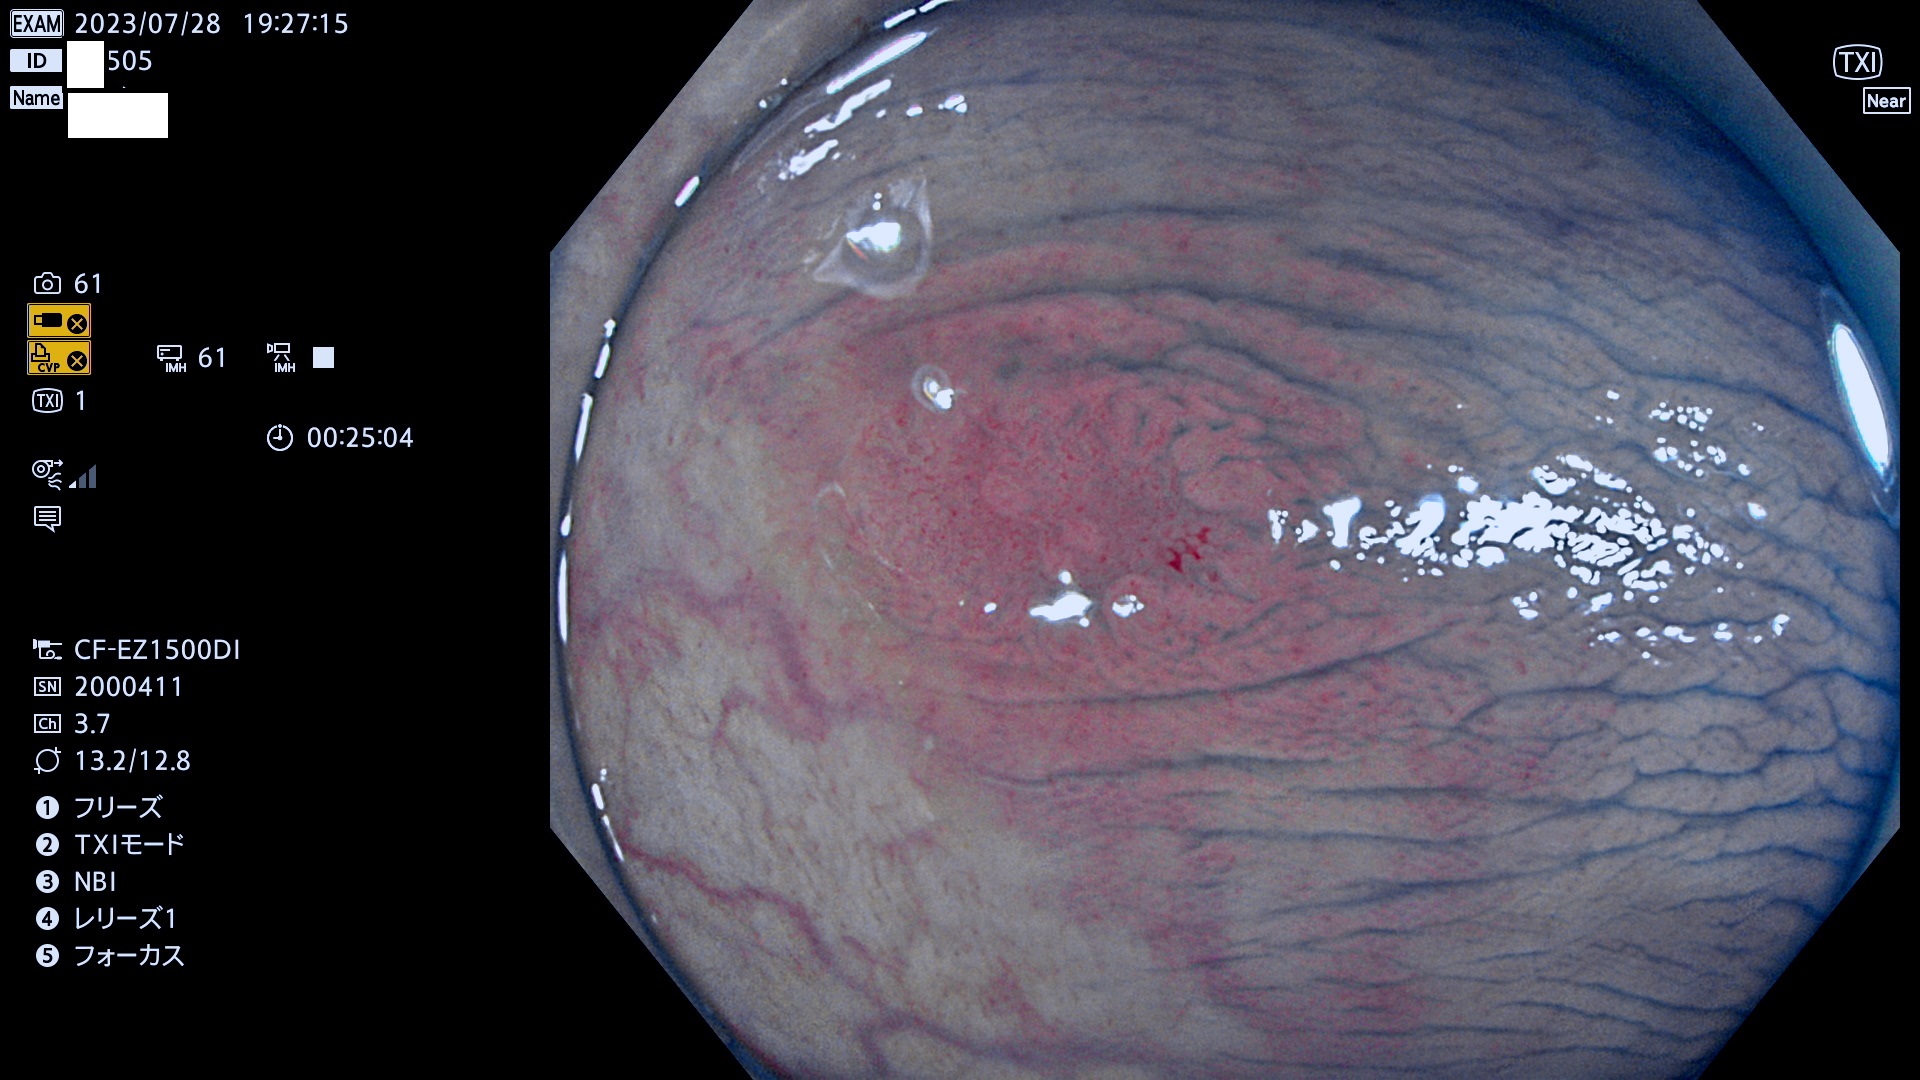

表面型腺腫(Flat Adenoma)の中で、完全に平坦な物をUb、陥凹している物をUcと呼びます。平坦隆起型(Ua)よりも、発見が難しく危険な病変です。このタイプは「内視鏡後・大腸癌の重要犯人」であり、この発見率は「腺腫発見率」よりも、重要な意味があります。

専門的)何故、陥凹していると危険? 癌遺伝子の変異が蓄積すると細胞分裂が盛んになり隆起するのでは?と通常は思われるでしょう。しかし実際は逆です。これは2022年の記事にある「細胞はストレスに直面したら細胞分裂を止める(細胞老化に入り休眠する)という生命の基本的現象」によるものです(Oncogene Stress)。細胞老化を起こすのが癌抑制遺伝子で、この安全装置(ブレーキ)が壊れると癌になります(休眠からの覚醒)。ですから陥凹は「まだ癌では無いが癌化の直前」を意味します。特に「小サイズなのに陥凹している」病変は短期間に腫瘍進化(⇒2021年記事)が起きたことを意味します(=ゲノム不安定性

専門的)Uc=De Novo癌? 内視鏡の解像度が低かった時代、このような説もありました。しかし今日の高精度内視鏡では良性の微小なUc型腺腫が日常的に見つかります。私見ですが「Ucこそが多段階発癌(Adenoma-Carcinoma Sequence)のMain Route」と考えます。

毎週の検査(木・金・土・日)に発見されたUb、Uc型・腺腫を、その週の日曜の夜にUPし1週間、提示します。

抽出の対象期間 2023年7月27日(木)〜7月30(日)の4日間(48件の検査)11件